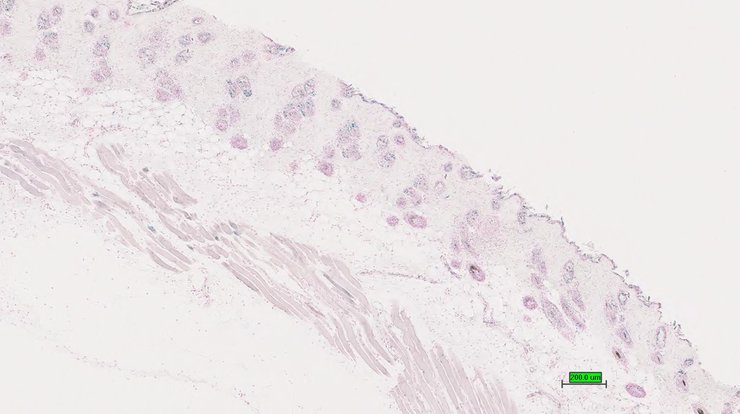

TS28: skin Present UC Davis_1880962

TS28: skin Present UC Davis_1880963

TS28: skin Present UC Davis_1880964

TS28: skin Absent UC Davis_1881025